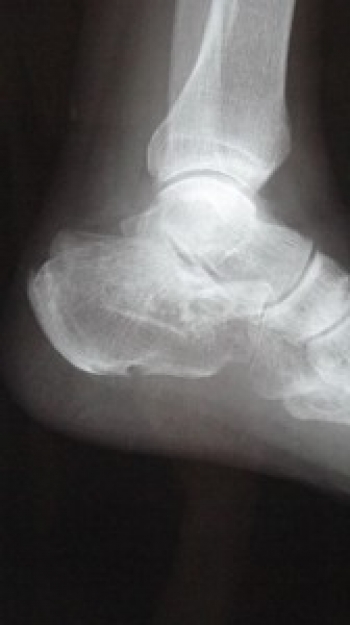

º£Æü¡¢¤´¾Ò²ð¤¹¤ë¤Î¤Ï¡¢Â­¡¦Â­»Ø¡¡ìû¹ü¹üÀޤˤĤ¤¤Æ¤´¾Ò²ð¤·¤Æ¤¤¤­¤Þ¤¹¡£

ìû¹ü¹üÀÞ

ìû¹ü¤Ï­º¬¹ü¤ÎÃæ¤ÇºÇÂç¤Î¹ü¤Ç¡¢Êâ¹Ô»þ¤ËºÇ½é¤ËÀÜÃϤ¹¤ëÉô°Ì¤Ë°ÌÃÖ¤·¡¢Â­º¬¹ü¹üÀÞÃæ¤â¤Ã¤È¤âÉÑÅÙ¤¬¹â¤¤¡£

µ÷¹ü¤Ê¤É¤ÈÊ£»¨¤Ê·ÁÂ֤δØÀáÌ̤òÍ­¤¹¤ë¤¿¤á¡¢¹üÀÞ¤¬À¸¤¸¤ë¤È´ØÀáÆâ¹üÀÞ¤òµ¯¤³¤·¤ä¤¹¤¤¡£

¤Þ¤¿¡¢¼þ°Ï¤òç§¡¦¿À·Ð¤â¿¿ô·Ð²á¤·¤Æ¤ª¤ê¡¢¤½¤Î¤¿¤á¸å°ä¾É¤âµ¯¤³¤·¤ä¤¹¤¤¡£

ȯÀ¸µ¡½ø¤Ë¤è¤êÀÔÄÇÄÇÂΰµÇ÷¹üÀÞ¤â¹çÊ»¤¹¤ë¤³¤È¤¬¤¢¤ë

ʬÎà¤Ï¡¢´ØÀá³°¹üÀÞ¡¢´ØÀáÆâ¹üÀÞ¤¬¤¢¤ë¡£